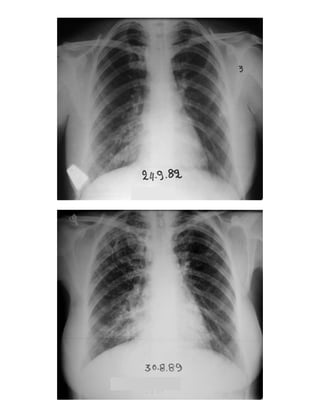

12. Περίπωση επαφής 574